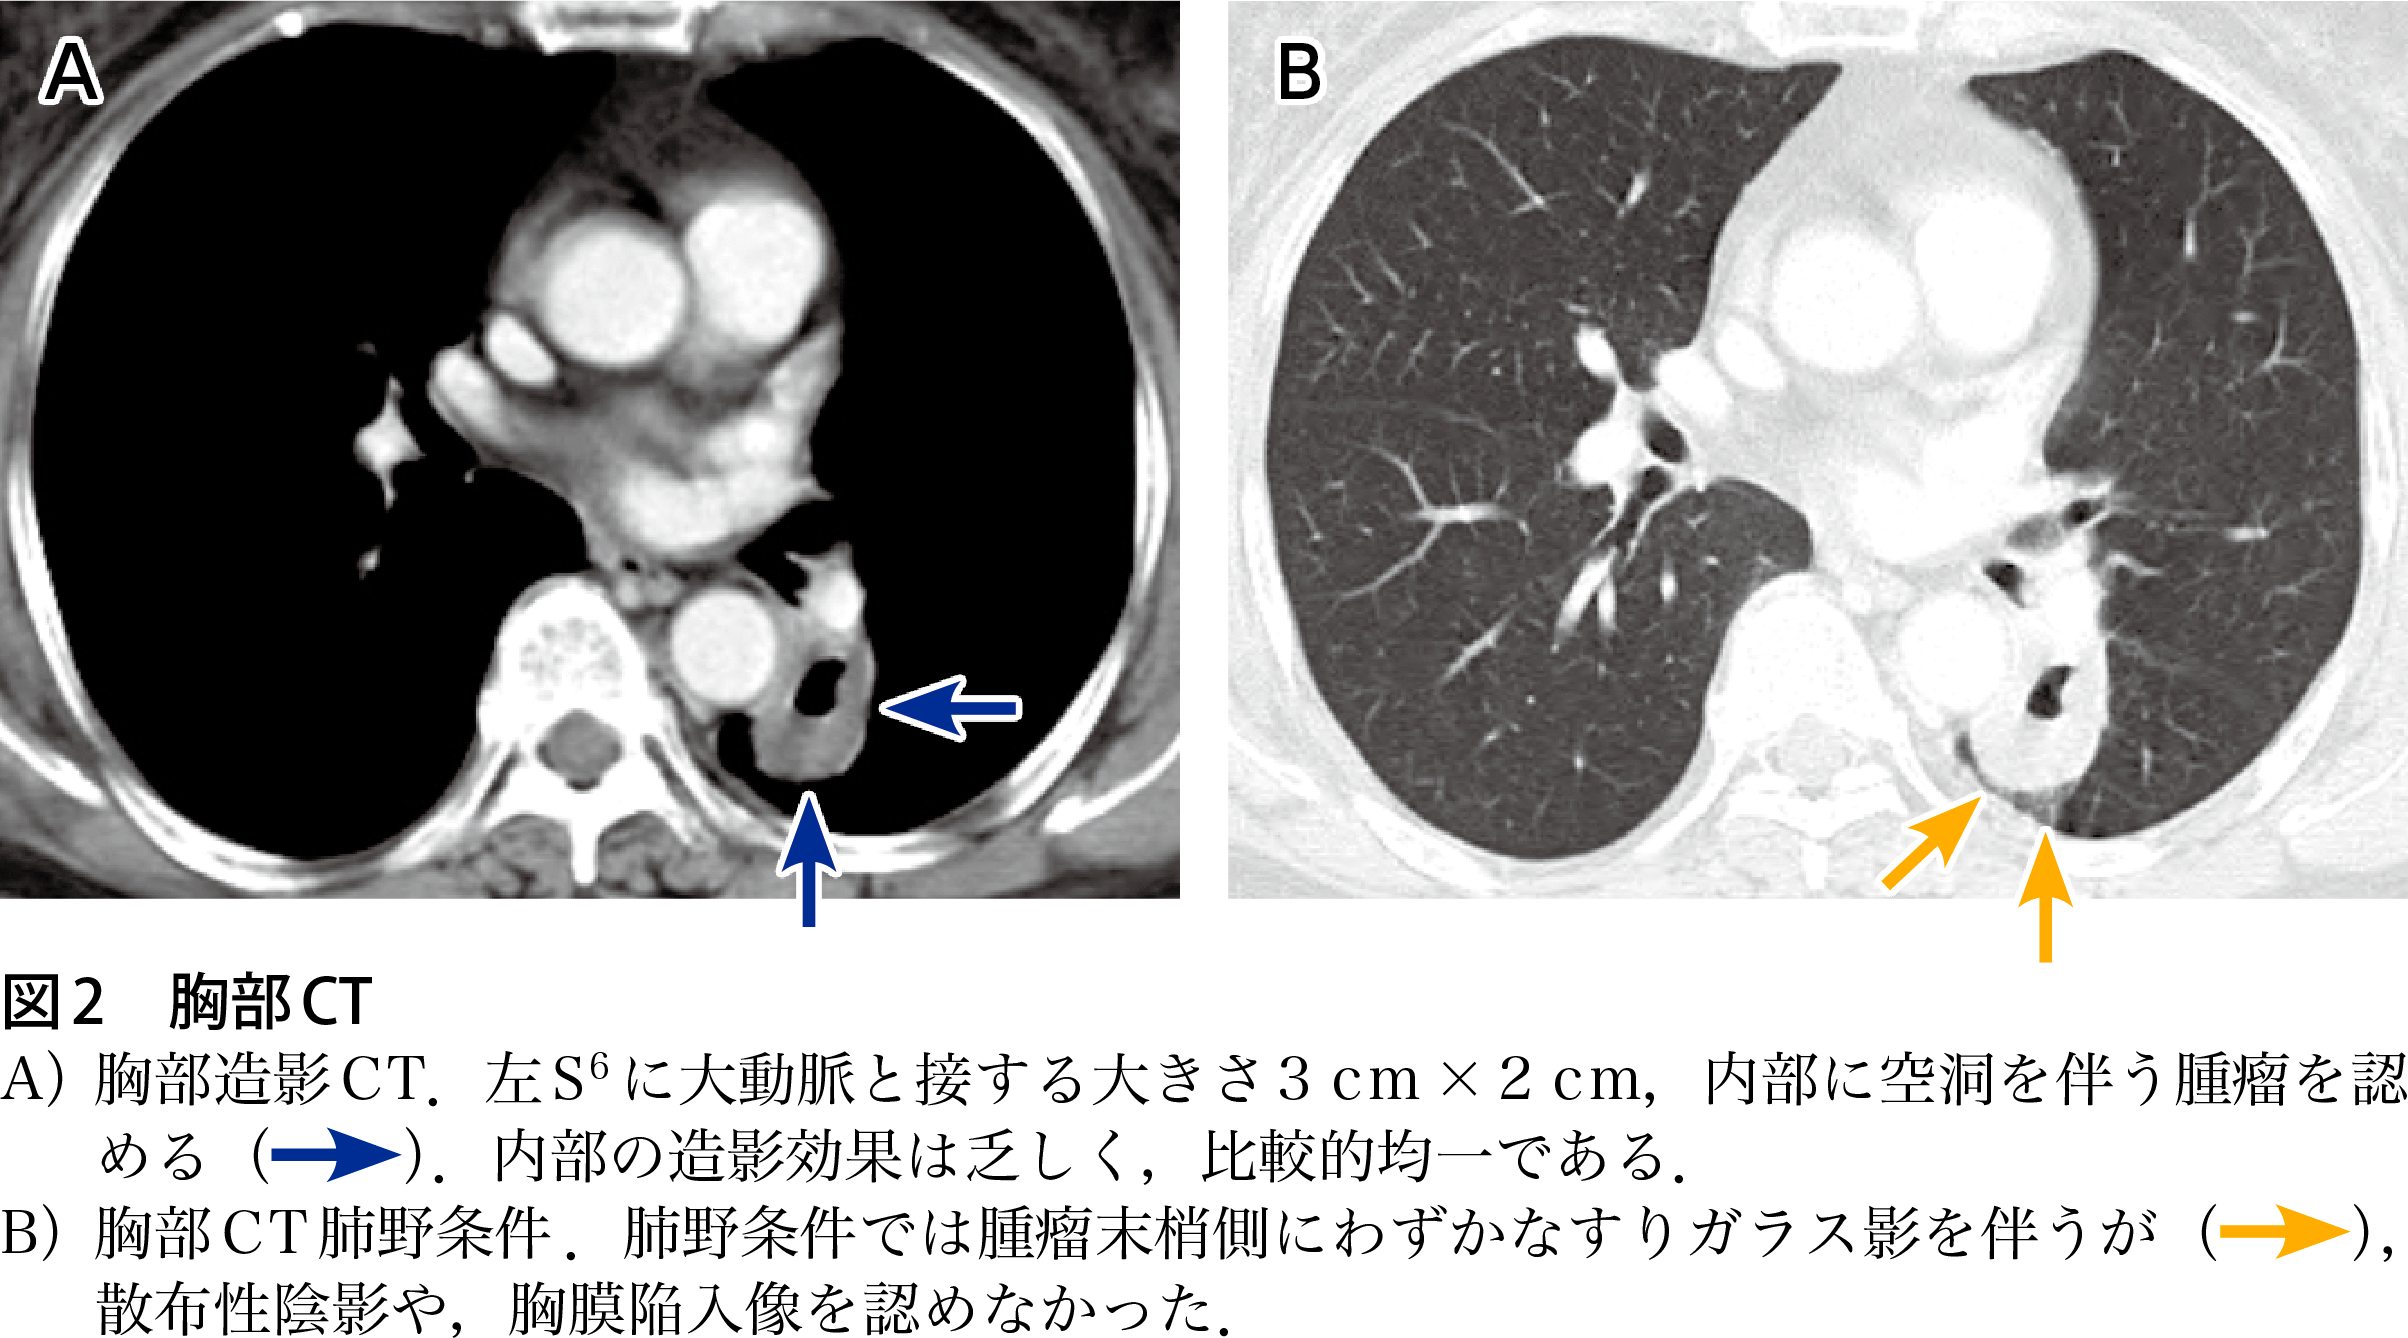

僧帽弁輪乾酪性石灰化の1例 胸部外科 69巻7号 医書 jp